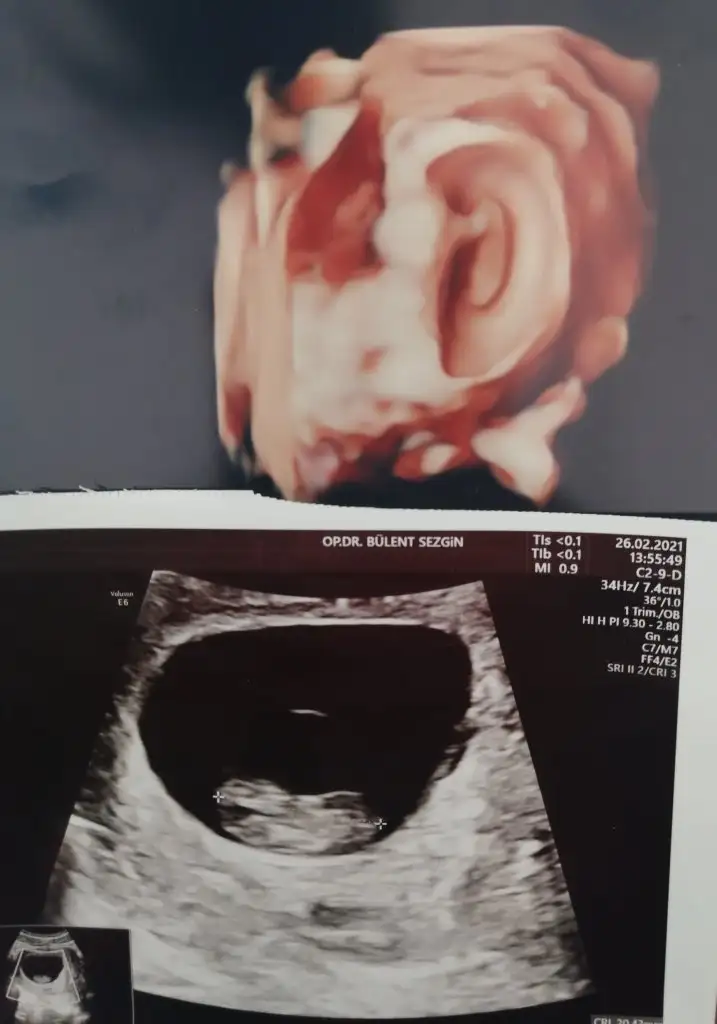

Geldim Aygülüm şükür Bi sorun yokmuş 8+5 göründü renkli usg ile baktı fasulye gibi bak atıyım hattaOradadır annesiBakalım doktor ne diyecek keyfi yerindemiymiş

Maşallah maşallahGeldim Aygülüm şükür Bi sorun yokmuş 8+5 göründü renkli usg ile baktı fasulye gibi bak atıyım hatta

Oyyy maşallahGeldim Aygülüm şükür Bi sorun yokmuş 8+5 göründü renkli usg ile baktı fasulye gibi bak atıyım hatta

Maşallah maşallahtek olduğu kesin yani

Hiç sorma her birine ayrı bakıyorum mucize gerçekten bunlarOyyy maşallahgüzel güzel büyüyor o kadar kıymetli ki ultrasonları toparlayıp albüm yapılmalı